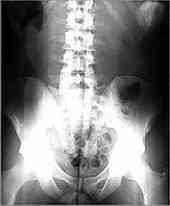

radiography

Synonyms: skiagraphy.

Definition: x-ray film of a pelvis (ray-dee-AW-graf-fee) Producing an image with radiation (usually by x-rays), sound waves (ultrasound), or other types of energy.